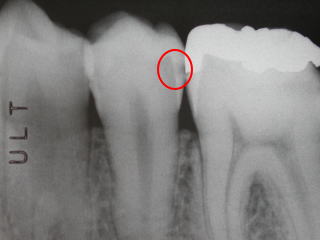

虫歯が発見されました。

初期なので経過を見ること

にしました。

1年経ちました。

1年経っても変化がないので

続けて経過をみることになりました。

2年経ちました。

黒い部分がはっきりしてきましたが

予防に努めました。

4年半後に虫歯の治療をしました。

最小限に削ることで対応ができました。

またこの4年間で虫歯を予防するコツを

つかみました。

神経をとらずに治療できましたが、

危ないところでした。